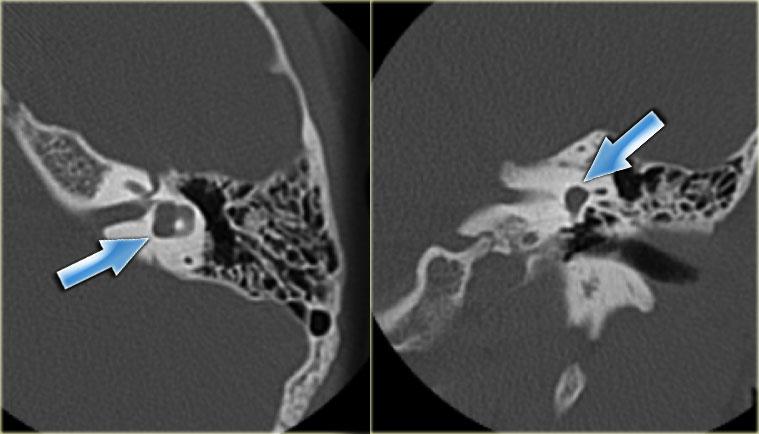

Ống đá chũm

Ống đá chũm hay còn gọi là ống dưới cung nối thông hang chũm với khoang sọ, chứa động mạch và tĩnh mạch dưới cung.

Đường kính của ống khoảng 0,5 mm.

Có thể nhầm lẫn với đường gãy xương.

Bên trái là hình ảnh của một bệnh nhân nữ 40 tuổi với xương chũm xơ cứng.

Ống đá chũm được nhìn thấy rõ ràng. (mũi tên)

Bên trái là hình ảnh xương chũm thông bào tốt.

Ống đá chũm khó phân biệt (mũi tên).

Bên trái là hình ảnh của một bệnh nhân khác với xương chũm xơ cứng.

Ống đá chũm được nhìn thấy rõ ràng.

Nếu bệnh nhân này là nạn nhân chấn thương, ống này có thể dễ dàng bị nhầm lẫn với đường gãy xương (mũi tên).